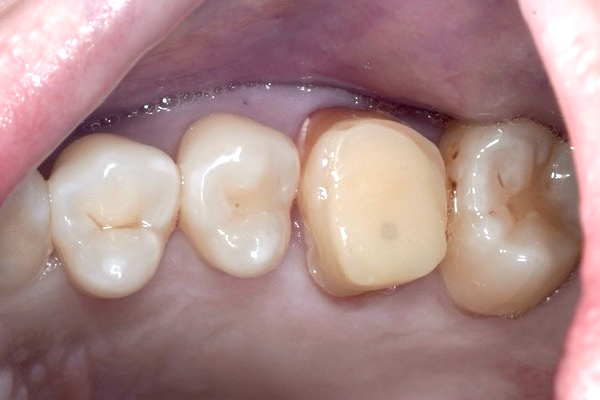

治療前(Before)

⚫︎根の先端に大きな病変があります。

⚫︎治療を行って治癒する見込みが低い状態です。

⚫︎前後の歯は削りたくないので、今後インプラント治療を行なっていきます。